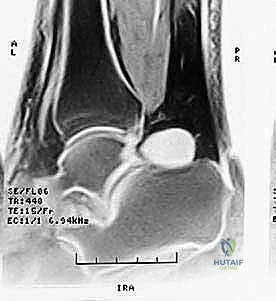

| الأشعة السينية (X-ray) | التقييم العظمي الأولي | يظهر العظم المثلثي، بروز ستيدا، الكسور القديمة، النتوءات العظمية. | أساسي ومبدئي. يتم التقاطه بوضعية الثني الأقصى للقدم لإثبات الانحشار الميكانيكي. |

| الرنين المغناطيسي (MRI) | تقييم الأنسجة الرخوة والالتهابات | يظهر وذمة نخاع العظم (Bone Marrow Edema) في العظم المثلثي، التهاب السائل المفصلي، التهاب وتر الـ FHL، وتمزق الأربطة. | المعيار الذهبي (Gold Standard) لتأكيد التشخيص وتحديد مدى تضرر الأنسجة المحيطة. |

شكل 3: صورة رنين مغناطيسي (MRI) تظهر بوضوح التورم والالتهاب (اللون الأبيض الساطع) في الأنسجة الرخوة والعظم المثلثي في الجزء الخلفي من الكاحل.